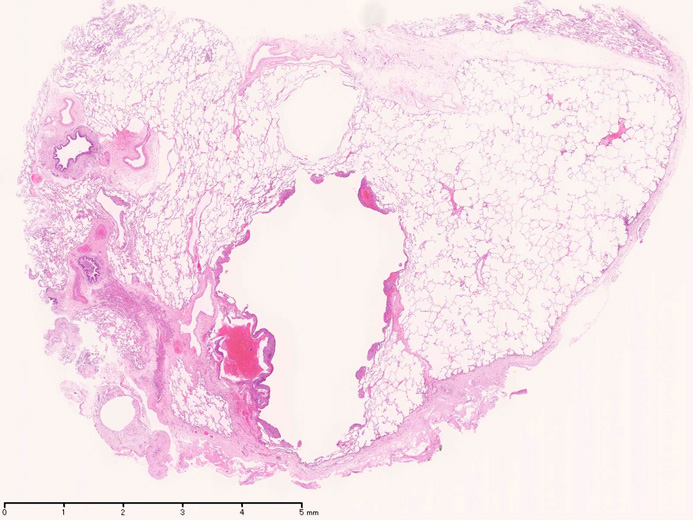

LAMの肺病変

嚢胞周囲または肺血管, リンパ管, 細気管支にそうLAM cellの浸潤, 集簇を特徴とする。LAM cellには2種類が認められ, 小型紡錘形細胞と細胞質の豊富な類上皮様細胞があり, 紡錘型は主に集簇巣の中心に存在し増殖能が高い。 類上皮様LAM cellは辺縁部に多く, 増殖能は低いがHMB45を強く発現している。

嚢胞形成はLAM cellの増殖と関連しており, 細胞が産生するmatrix metalloproteinases(MMPs)による組織破壊によるらしい。